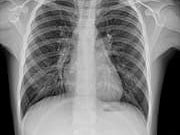

This population-based case-control study of more than 3000 people found that statins increased the risk of pneumonia1 by 26%, and increased severe cases of pneumonia requiring hospitalization by 61%.

Statins Increase the Risk for Pneumonia